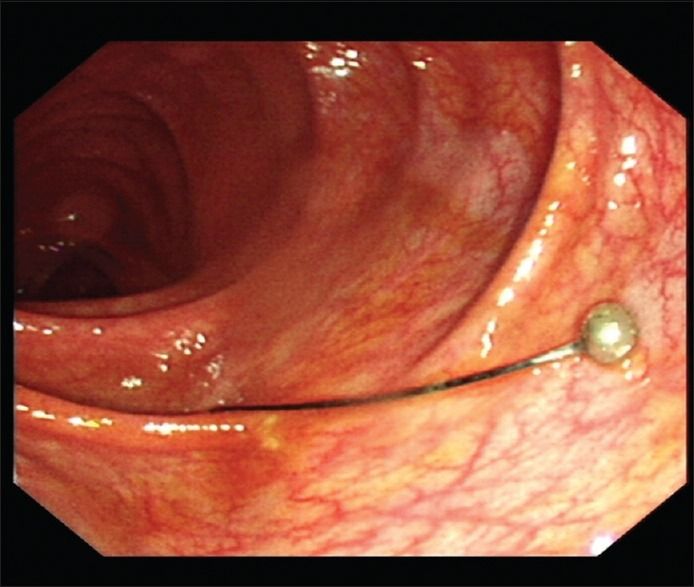

В публикации[1] доктора из Саудовской Аравии представлен опыт диагностики и лечения 13-летней пациентки, которая была госпитализирована через 48 часов после того, как случайно проглотила булавку для платка. Она жаловалась на жар и умеренную боль в животе, тошноту. При обследовании зафиксированы: температура тела — 38,6 °С, артериальное давление — 102/60 мм рт. ст., частота сердечных сокращений в покое — 118 ударов в минуту, частота дыхания — 20 дыхательных движений в минуту. При пальпации живот мягкий, не напряжен. Результаты анализа крови: гемоглобин — 125 г/л, лейкоциты — 7,4 × 109 клеток/л. При рентгенографии органов брюшной полости в тонкой кишке обнаружена булавка, это подтвердила и КТ живота (рис. 1). В ходе динамического наблюдения отмечено продвижение булавки в толстую кишку (рис. 2). В течение 4 дней, пока ИТ оставалось в восходящей ободочной кишке, пациентка продолжала жаловаться на боли в животе. В связи с этим ей была назначена колоноскопия, которая обнаружила булавку в восходящей ободочной кишке, в нескольких сантиметрах от слепой кишки. Повреждений слизистой оболочки зафиксировано не было, булавка была успешно извлечена с помощью щипцов «крысиный зуб» (рис. 3).

Рисунок 3.